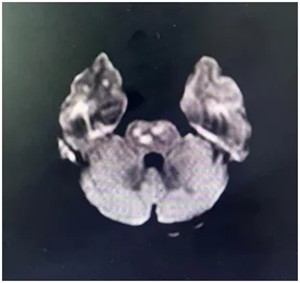

▲ MRA显示:基底动脉及右侧椎动脉不显影,右侧大脑中动脉不显影